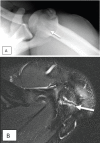

Collegiate American football player with shoulder pain and known lesser tuberosity avulsion. (A) Axillary shoulder radiograph performed to follow up lesser tuberosity avulsion demonstrates an unfused apophysis (arrow) at the acromion. (B) Follow up MRI demonstrates edema at the apophysis (arrow), consistent with acromial apophysiolysis.

Figure 4.

13-year-old baseball pitcher. AP radiograph of the (A) right shoulder shows diffuse widening of the right proximal humeral physis (arrow). (B) For comparison, the left shoulder demonstrates normal width of the physis.